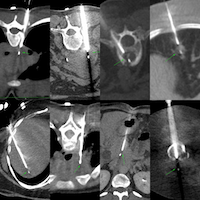

Biopsy of retroperitoneal fibrosis is possible under CT guidance

The video describes the case, the final diagnosis, 4 other similar cases, one with an anterior approach with one new reference.